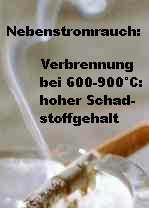

Zigarette mit Nebenstromrauch: Verbrennung bei 600-900°C produziert hohe Schadstoffwerte. [8a]

<In der 600 bis 900 Grad heissen Glut einer Zigarette entstehen [vor allem an der Spitze der Zigarette] aus eigentlich harmlosen Substanzen wie in einem chemischen Reaktor viele neue Verbindungen, die sucht- und krebserzeugend sein können. 3044 chemische Substanzen haben Wissenschaftler in einer Zigarette gefunden. Aus diesen wiederum bilden sich bis zu 4800 chemische Stoffe, die im blauen Dunst einer Zigarette umherschweben.>

Der Rauch der Zigarette, die an der Zigarettenspitze einfach abbrennt, ohne dass daran "gezogen" wird, ist der schlimmste, also der Nebenstromrauch bzw. Seitenstromrauch:

(http://www.surfmed.at/?news/1a2941b25a9ad7a9728df8135da85b50)

-- der Tabak verbrennt nur unvollständig

-- zahlreiche Giftstoffe gelangen in die Luft.

(Passivrauch: Eigenschaften und Folgen; http://www.proaere.ch/d/data/data_36.pdf)

Die Schadstoffe aus dem Nebenstromrauch / Seitenstromrauch gelangen ungefiltert in die Luft. Die Schadstoffkonzentration im Nebenstromrauch / Seitenstromrauch ist deswegen z.T. massiv höher als im inhalierten Rauch, der vom Raucher wieder ausgeatmet wird.

<Etwa drei Viertel der Zigarette verbrennt als Nebenstrom durch das Glimmen der Zigarette. Die Konzentration der Schadstoffe im Nebenstrom der Zigarette ist bis um das 30- bis 100-fache höher als im Hauptstrom. Die Bestandteile des Passivrauchs verbleiben lange in der Raumluft. 2 Stunden nach dem Rauch sind noch 50% der anfänglichen Konzentrationen von Stickoxiden in der Raumluft enthalten.>